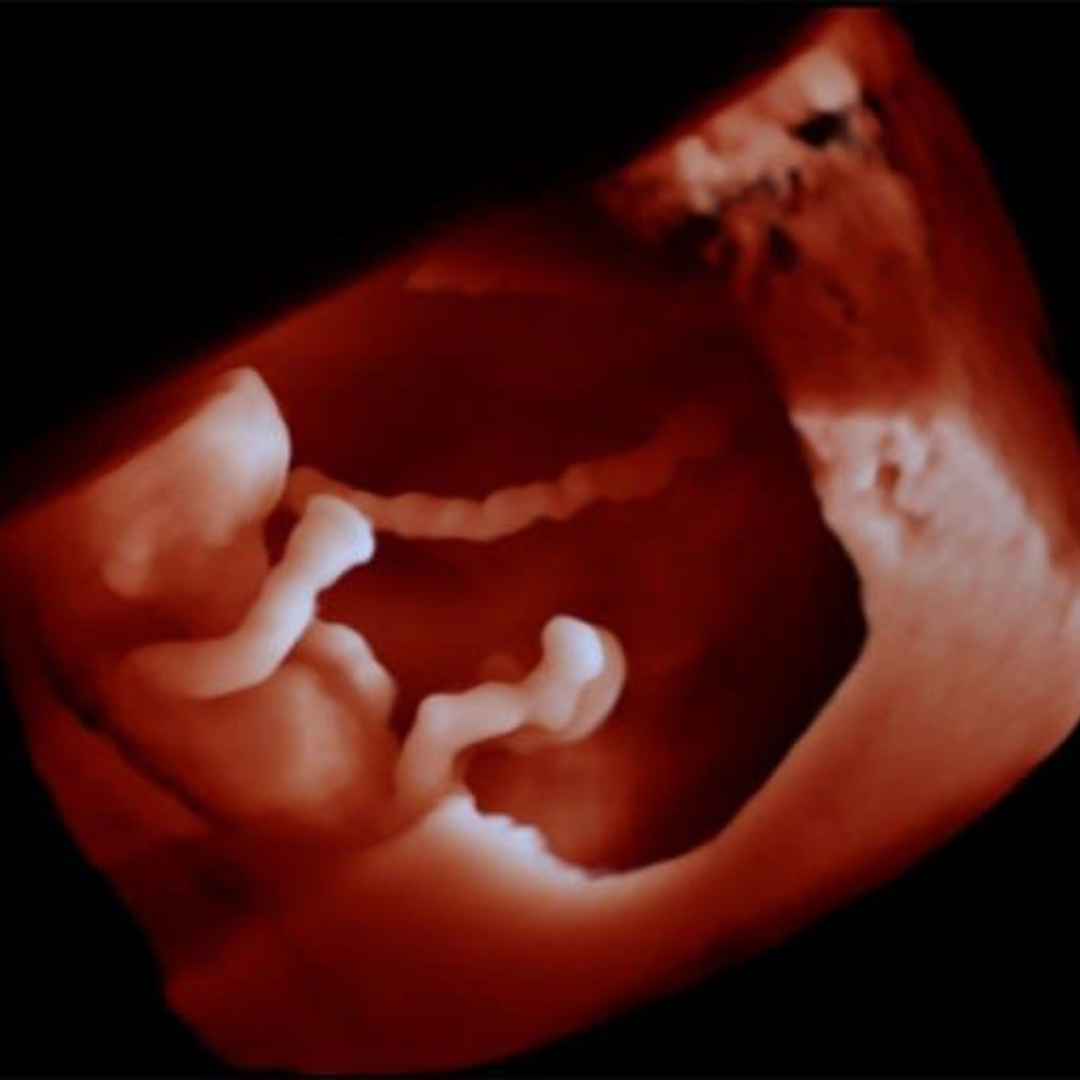

Transvaginal 6D

Realizarlo entre las 5 a 10 semanas.

Disfruta y llévate grandes recuerdos con las maravillosas imágenes de tu bebé en sus primeras semanas, La tecnología GlassVue nos muestra impresionantes tomas sobre el saco gestacional, el embrión y detección de hematomas u otras patologías incipientes.

| 6D | Obtener imágenes de la estructura del embrión a color con volumen, en lugar de imágenes planas en tiempo real aportando una mayor capacidad de diagnóstico y por otro lado se ha demostrado el alto impacto que genera en el vínculo materno fetal. |